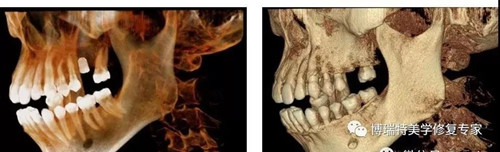

智能3D全景CBCT 多金属去伪影图

普通CBCT 多金属去伪影图(同一患者)